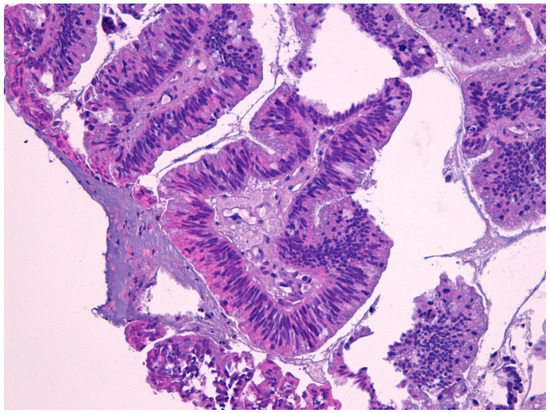

4.5. Intestinal Adenocarcinoma

4.6. Non-Intestinal Adenocarcinomas